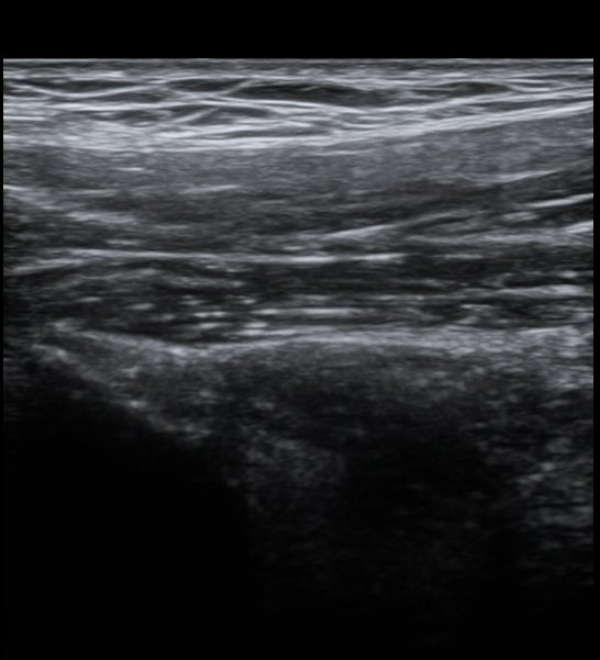

´ëÅðÁ÷±Ù ÈûÁ٠Ⱦ´Ü¸é °Ë»ç¿¡¼­µµ ÈûÁÙÀÇ Àú¿¡ÄÚ º¯È­¸¦ º¸À̰í(»çÁø 4, 5) ÀÌ º´Àû º¯È­µµ

°ÇÃø(»çÁø 6, 7)°ú ºñ±³ÇÏ¸é ½±°Ô ÆÇ´ÜµÈ´Ù.